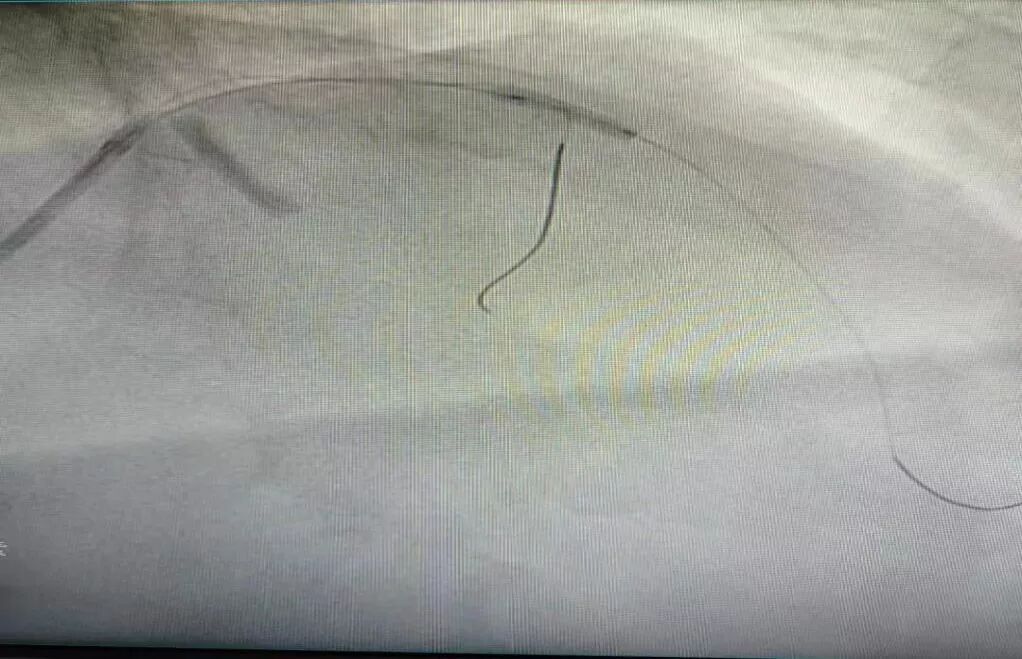

(7)2018年11月28日开展第一例下腔静脉滤器植入术。

患者:魏某  男性  52岁 平陌镇